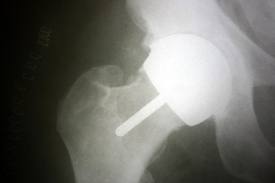

His attitude after an x-ray that was “perfect” was that my pain was coming from my back. That my metal testing hadn’t been done in the right lab so the results were not reliable.

I sought the opinion of another surgeon (with lots of reparative experience) and the only logical solution seemed to be to have a total hip replacement with a prosthesis that was not metal on metal.

He felt strongly that I had metallosis from the prosthesis. On August 15th I had a revision of my metal on metal to a ceramic on “plastic” total hip.